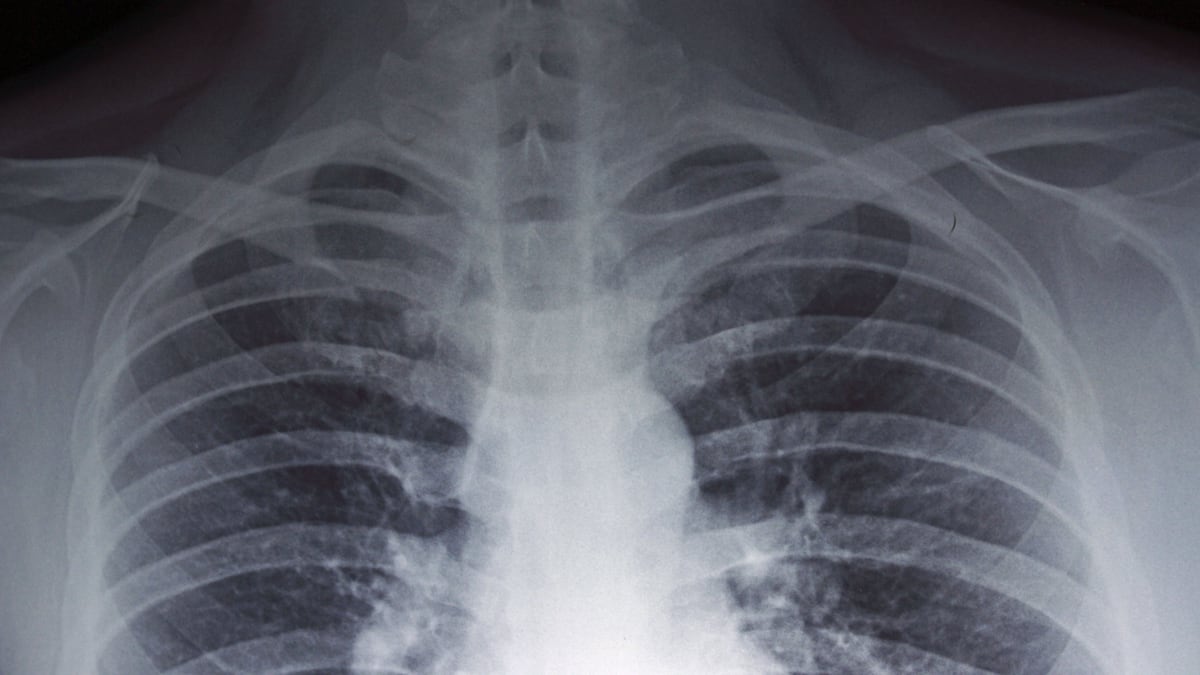

En cuanto a los síntomas característicos de la enfermedad, existen similitudes con respecto a la neumonía, por lo cual encendió las alertas y escaló la preocupación en el país: fiebre, dolores musculares y abdominales, así como dificultad respiratoria.